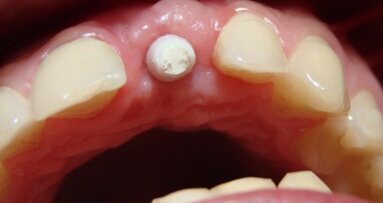

Po upływie 22 miesięcy od wykonania finalnej rekonstrukcji protetycznej doszło do poprzecznego pęknięcia korzenia zęba #12. Podjęto decyzję o natychmiastowej implantacji w tym miejscu. Wybrano poddziąsłowy protokół gojenia. Pacjentka nie wyraziła zgody na wykonanie przeszczepu łącznotkankowego celem zwiększenia objętości dziąsła związanego w okolicy przyszyjkowej implantu.

Odsłonięcia struktur kostnych dokonano poprzez wykonanie nacięcia poprowadzonego podniebiennie od szczytu wyrostka bez wykonywania horyzontalnych cięć odbarczających. Wprowadzony został implant Astra 3,5 mm (AstraTech AB, Szwecja), a powstała od strony przedsionkowej dehiscencja i fenestracja została pokryta materiałem BioOss (Geistlich Pharma, Szwajcaria) oraz membraną resorbowalną BioGide. Rana została zaszyta szwami pojedynczymi.

Zaplanowano 16-tygodniowy okres gojenia. Na czas gojenia wykonano odbudowę tymczasową, wykorzystując koronę z utraconego filaru.

Ryciny pokazują sytuację po odsłonięciu implantu i 2-tygodniowym okresie gojenia z wykorzystaniem śruby gojącej. Na implancie wykonano koronę tymczasową z kompozytu, co umożliwiło jej łatwą modyfikację w gabinecie. Stwierdzono prawie 2 mm recesję dziąsła oraz brak brodawek dziąsłowych przy zębach sąsiednich.